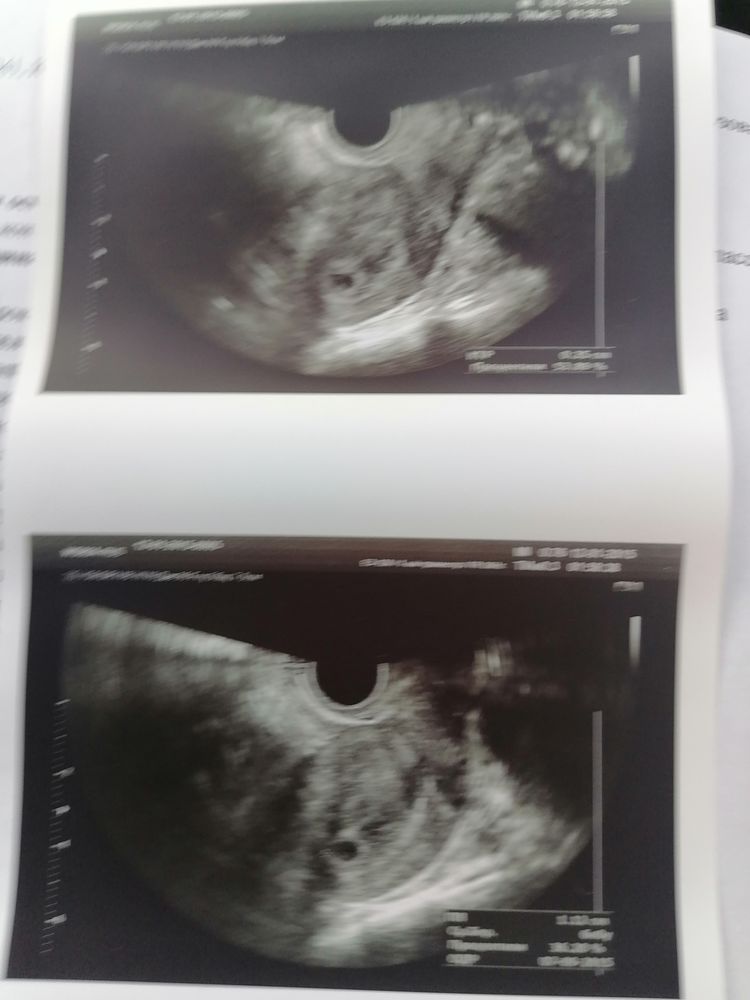

Узи на 23 дпп

Улыбаюсь с вами, прям малыш малыш!!! ого го какой, растите еще больше и здоровенькими, это прекрасно)